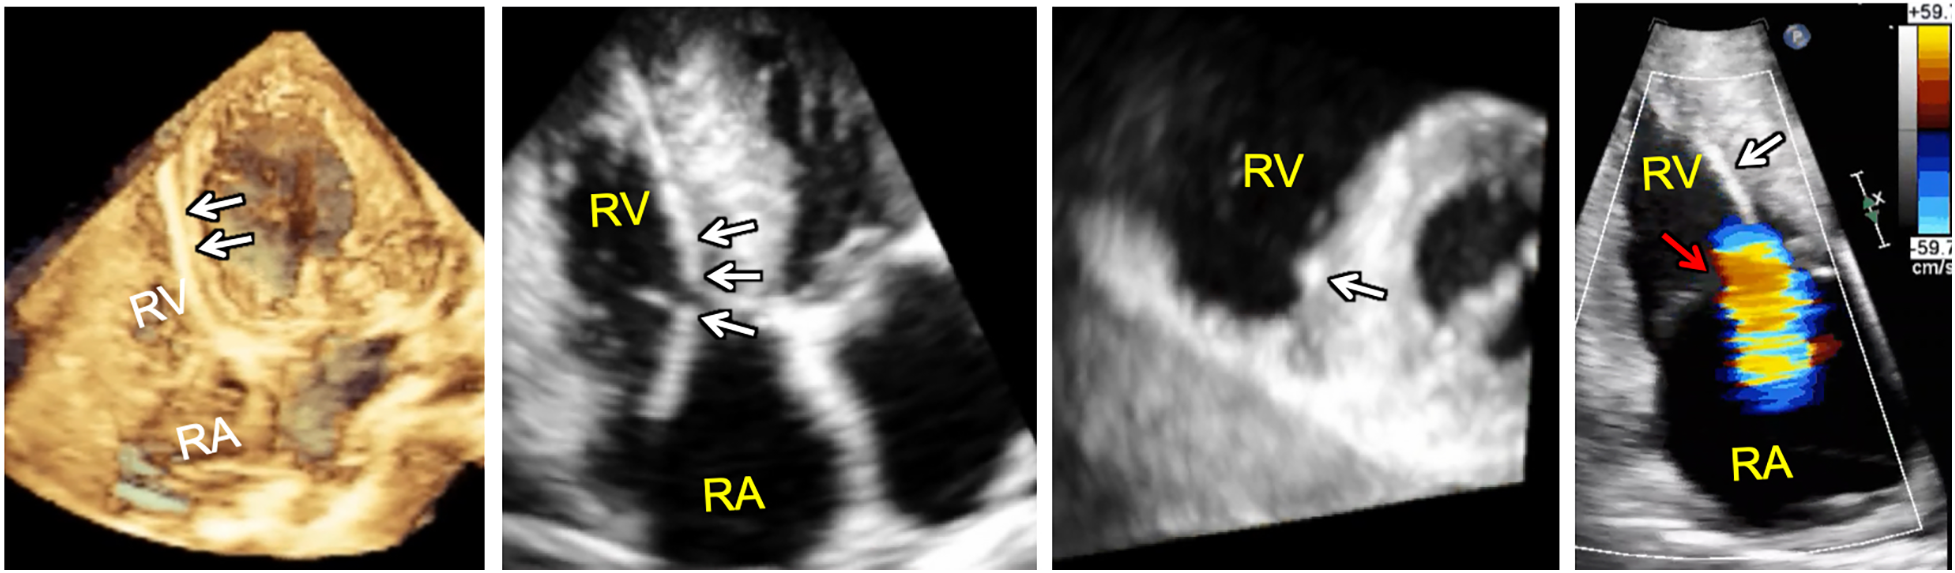

Device-lead related interference with the tricuspid valve apparatus is a potential complication that is incompletely described by 2DE as the device-lead is really only seen in its entirety in less than 20% of cases (49). The addition of 3D RV imaging has improved non-invasive assessment of the relationship between the tricuspid apparatus and device leads enabling direct visualization of the both the TV leaflets and the sub-tricuspid apparatus making it possible to determine the presence or absence of interference in select cases (50–52). According to one study, leads demonstrating leaflet impingement on 3DE were associated with a greater degree of TR with a median vena contracta of 0.62 cm compared to 0.27 cm in patients without 3DE evidence of lead-related leaflet interference. Importantly, positioning of the lead in the commissure resulted in less frequent interaction, suggesting that echocardiographic guidance of or follow-up after lead placement may be beneficial in some cases (52). More recent data suggests that lead-related tricuspid valve interference can be associated with the tricuspid valve leaflet(s) alone, the sub-tricuspid apparatus alone, or both the leaflet(s) and the sub-tricuspid apparatus (Figure 9) (53).

Figure 9

3D full volume dataset of the right ventricle (far left) and adjacent cut planes through the 3D dataset (left, middle and right, middle) showing device-lead (white arrows) impinging on the septal leaflet and sub-tricuspid apparatus in the region of the right ventricular septum resulting in tricuspid regurgitation (far right). Note that the tricuspid leaflet coaptation zone (red arrow) is not the origin of tricuspid regurgitation in this case. In fact, tricuspid regurgitation is originating at the point of device-lead contact with the septal leaflet.